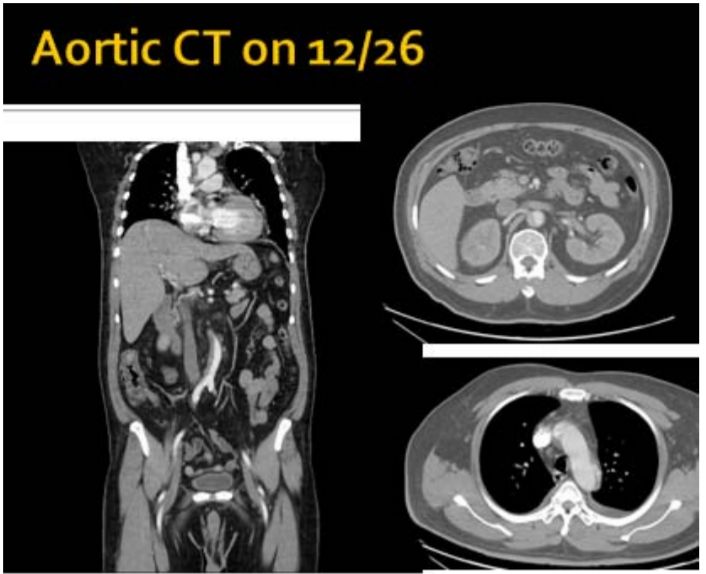

5. 病人男性59歲於午夜24時,突因胸悶並有牙床緊疼,乃直往急診部求診,時病人之T/P/R = 35.1/51/18, BP 137/74 mmHg; 理學檢查,未見任何異常。病史追尋,本病人曾經醫師確定高血壓、高脂血、糖尿病及攝護腺肥大,唯僅只服用Bisoprolol 2.5 mg/day。經緊急檢查:其心電圖及胸部X光顯示如圖:生化檢查: CK,96 U/L;CK-MB,20 U/L;TnI <0.0012 ng/ml;Sugar 252 mg/dL; Na,137 mmol/L; K, 3.7 mmol/L; TG,182 mg/dL and Total cholesterol, 222 mg/dL ; 血液檢查: Hb,13.9 g/dl; Platelet, 203 K/uL; WBC,9.45 K/uL; Cre,1.3 mg/dL 請問本病人最可能的急診診斷是:

(A) Printzmetal's angina (B) Aortic dissection (C) Acute anterior myocardial infarction (D) Hypertension (E) Acute periodontitis disease